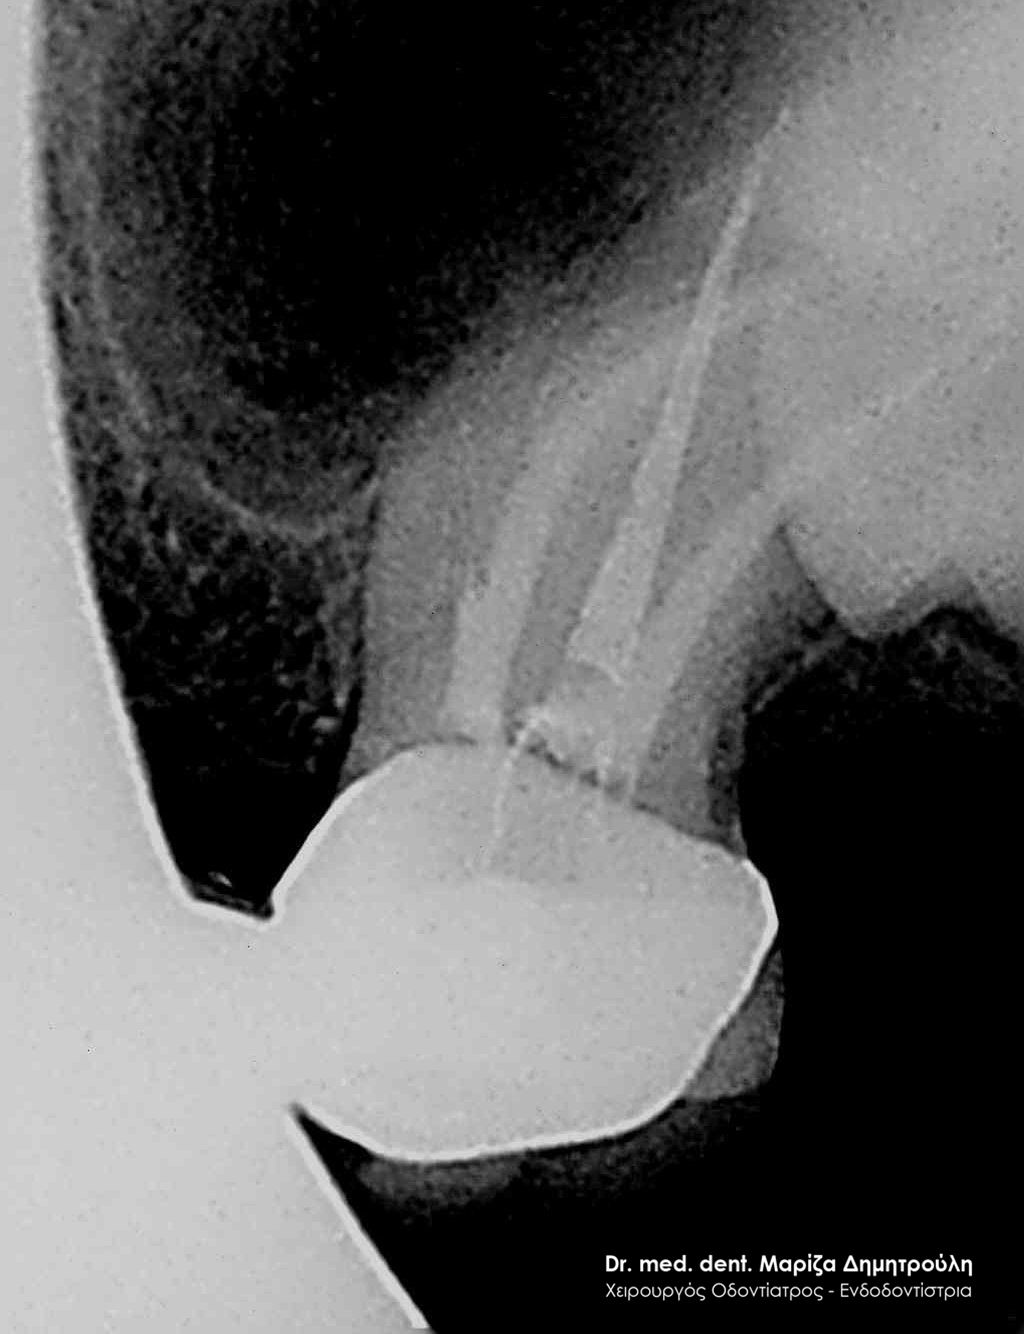

Clinical photo after the root canal filling